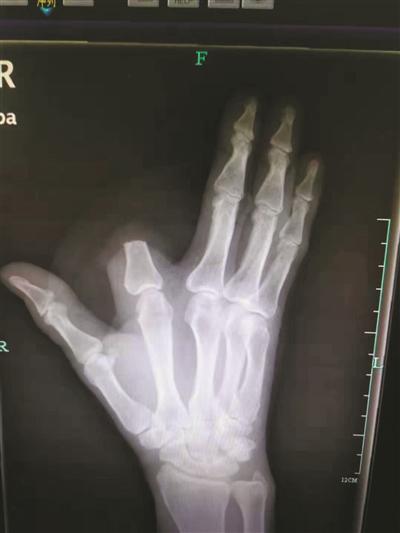

右手x片图片

右手x片图片,正常右手x光片

手术前x光片 右手2,4指完全离断,第4指大部分挫灭.

x光片显示,患者右手环指离断

正常右手x光片

右手x光片